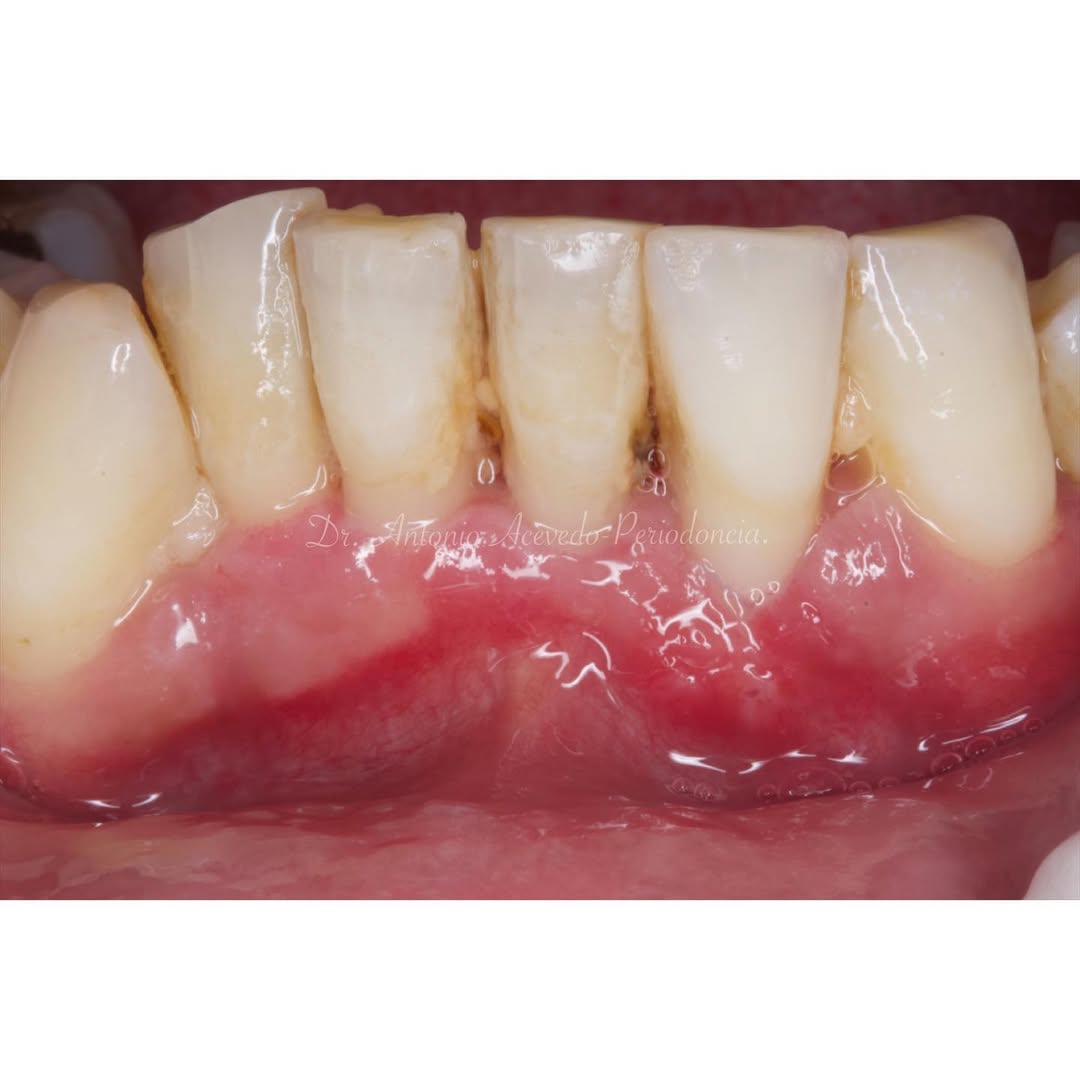

En esta estancia clínica aprenderás a hacer una vestibuloplastia con un injerto gingival libre sobre dientes en el 5º sextante y frenectomía del frenillo labial, con el objetivo de ganar encía queratinizada.

Te enseñaré el paso a paso para obtener los conocimientos para poder ofrecer este